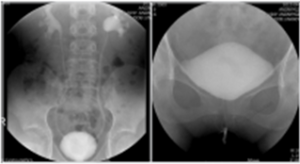

Grade of VUR

좌측 그림은 방광요관역류 (우측 grade II, 좌측 grade IV)가 있는 4세여아의 배설성방광요도조영술 (voiding cystourethrography) 사진이고 우측 그림은 자궁절제술 을 시행하고 지속적인 질누출을 호소하는 환자에서 보이는 방광질루 (vesicovaginal fistula) 소견이다. 우측 그림에서 환자의 방광은 배뇨를 시작하지 않은 상태 (funneling 및 bladder neck opening 이 되지 않은 상태)에서 질로 요누출이 관찰되고 있다.